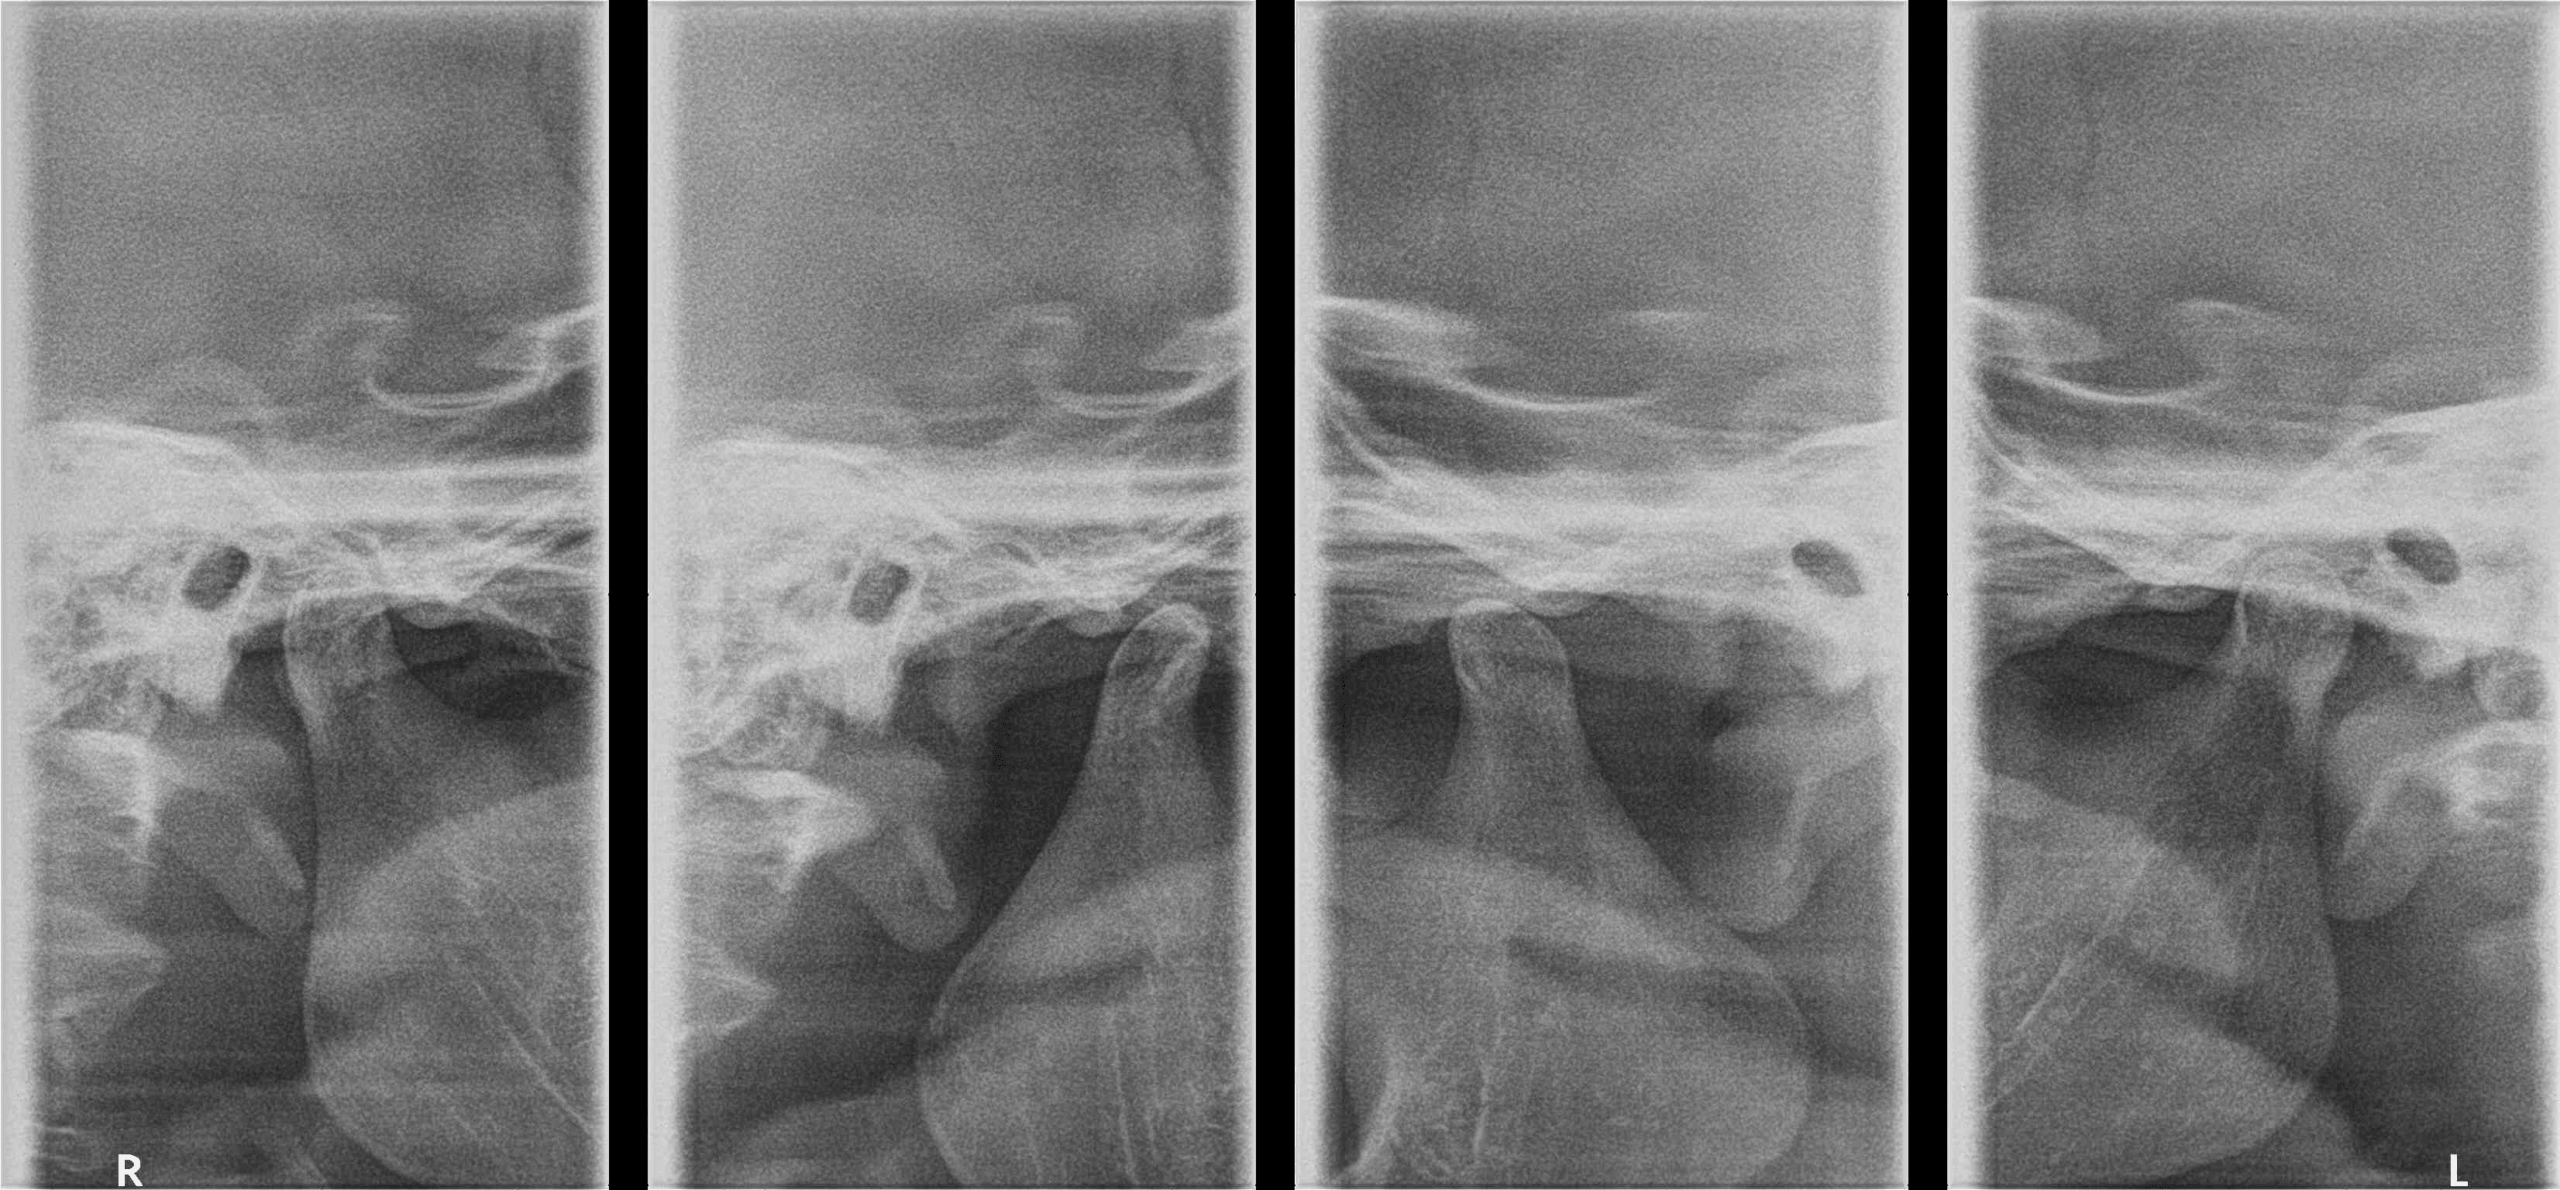

RADIOGRAFÍA DE ATM LATERAL BOCA ABIERTA Y CERRADA O COMPARATIVA DE ATM

Esta radiografía sirve para evaluar la articulación temporomandibular desde una vista lateral

Entre sus principales indicaciones se encuentran:

- Evaluar cambios de los componentes óseos articulares

- Detección de patologías articulares

- Evaluación del espacio articular

- Evaluación de la trayectoria condilar

Ventajas:

La ventaja principal es que es una radiografía que se enfoca en la ATM, en la cual se puede observar la estructura ósea tanto del cóndilo mandibular como de la cavidad glenoidea.